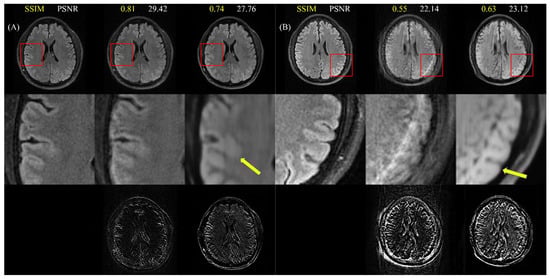

4.3. Visual Reading

4.4. Cross-Dataset Generalization